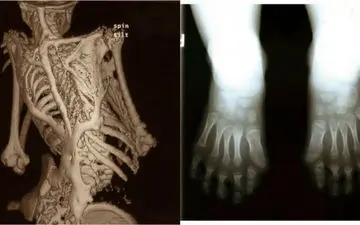

نوزاد بریتانیایی به دلیل اختلال ژنتیکی در حال سنگ شدن می باشد.